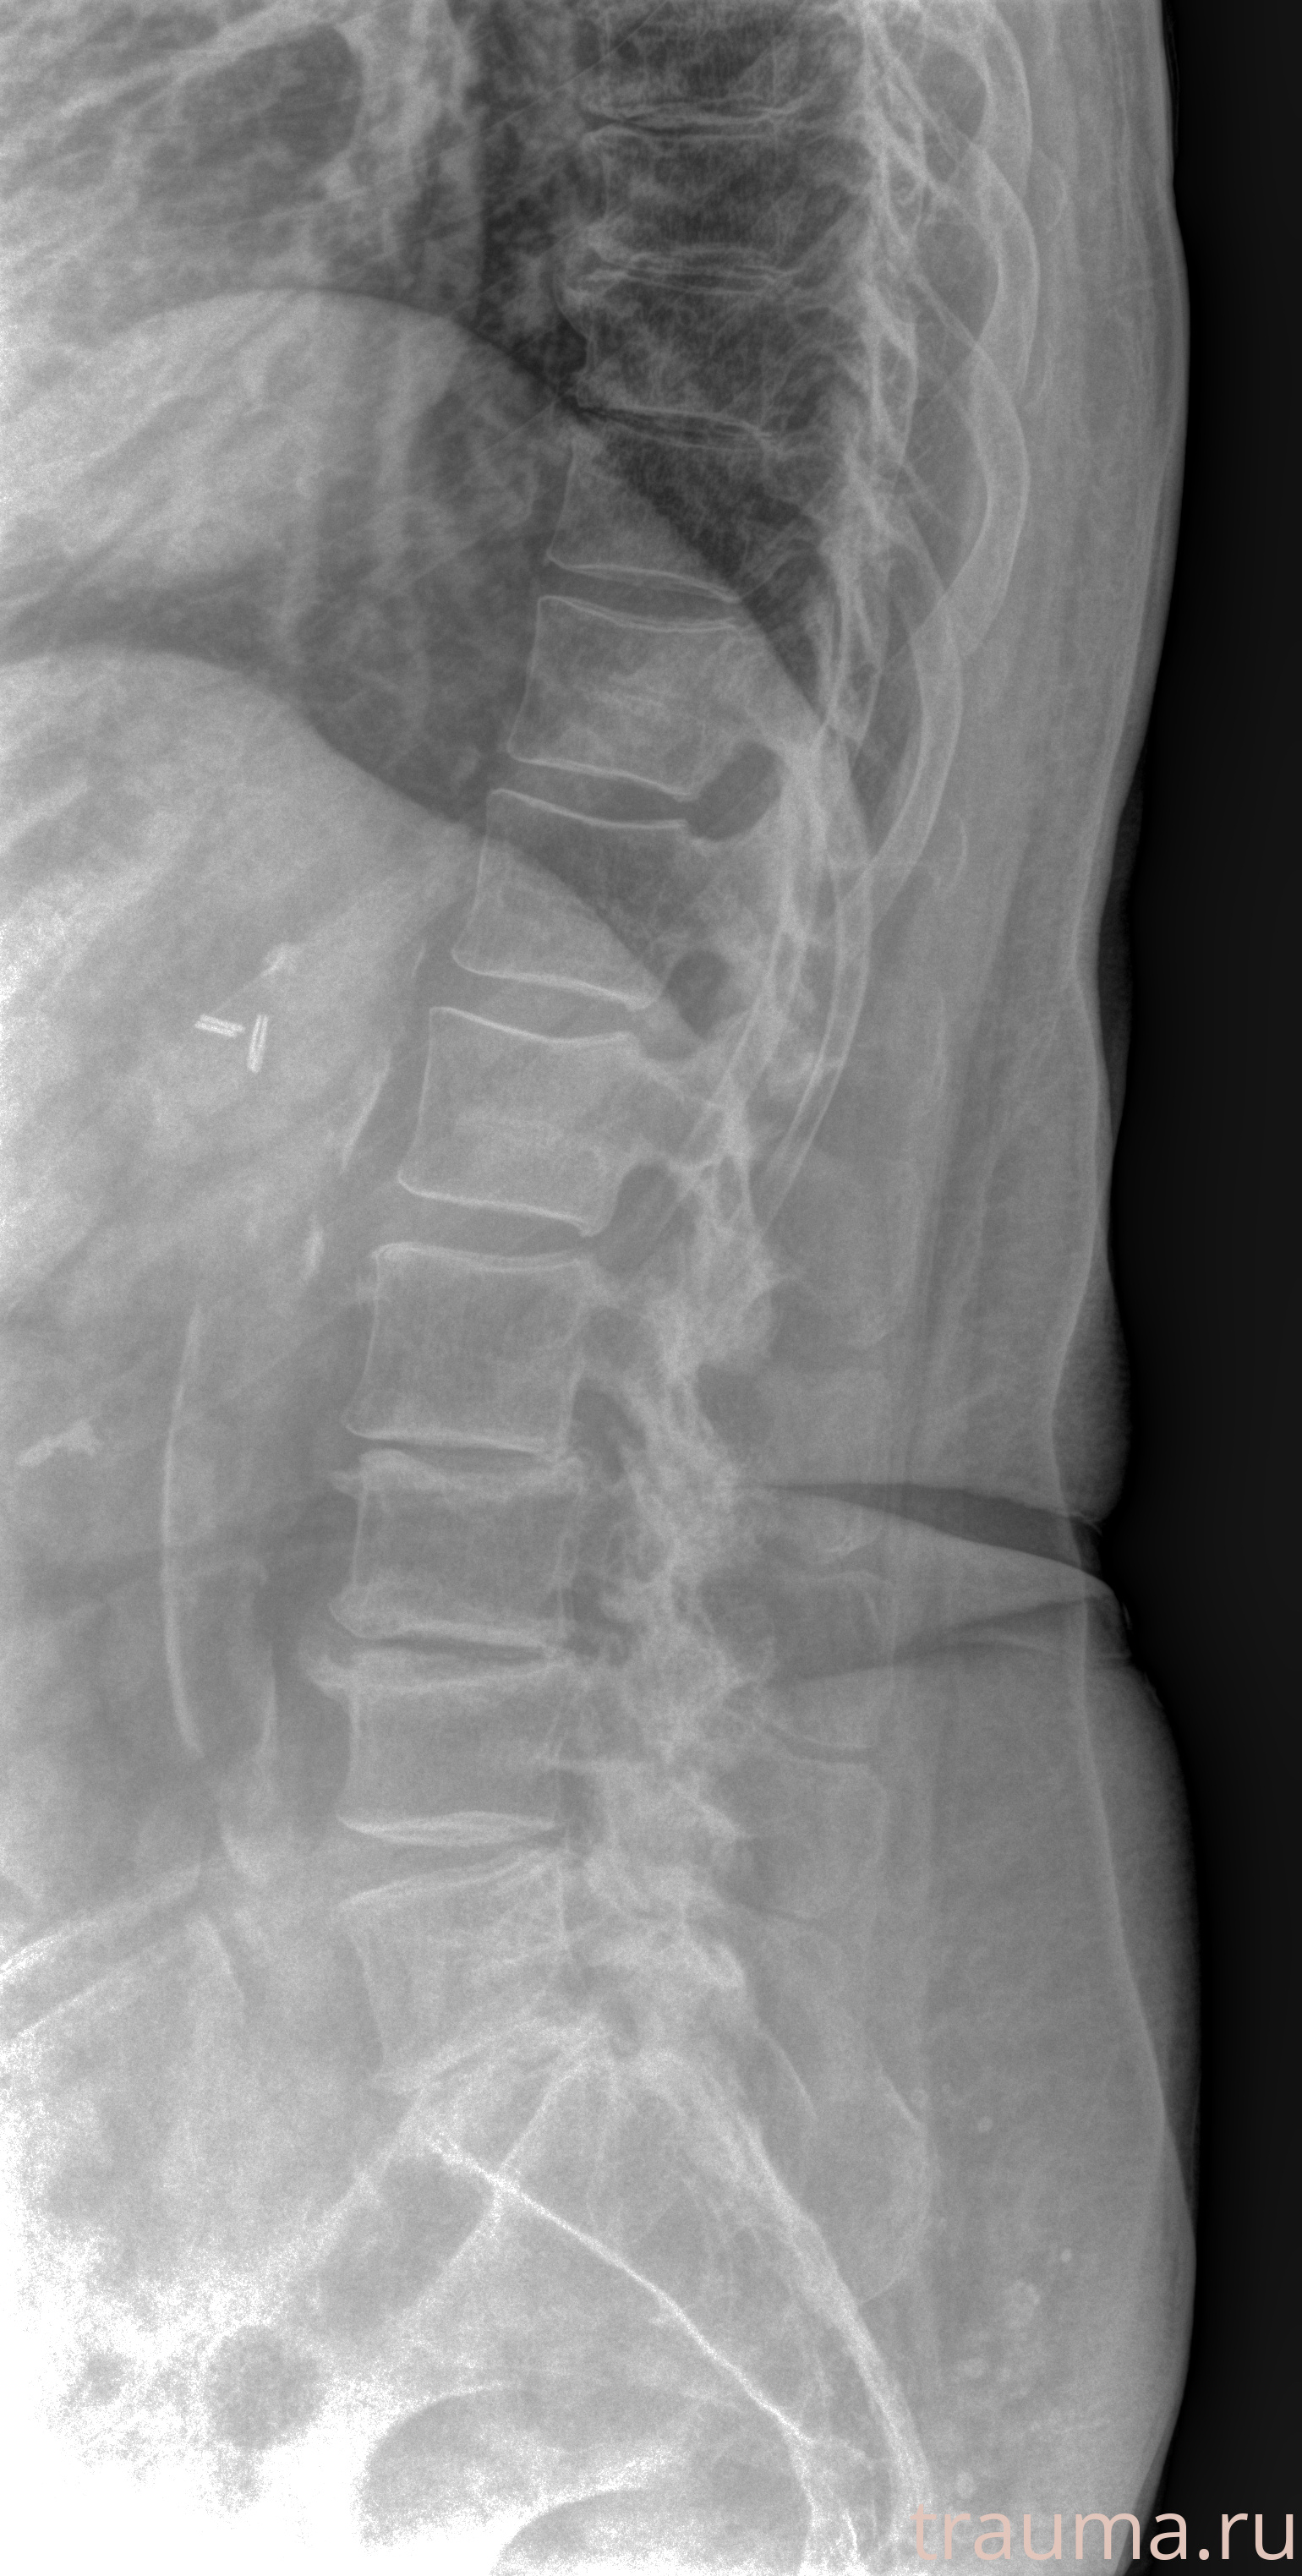

Рентгенограммы

Рентген на дому: по вашему адресу приезжает врач-рентгенолог, травматолог-ортопед с мобильным рентгеновским аппаратом, проводит диагностику травмы или заболевания, делает необходимые рентгенограммы, дает рекомендации по дальнейшему лечению. Получить качественные снимки в домашних условиях возможно благодаря уникальной методике, разработанной МосРентген Центром для института  Склифосовского